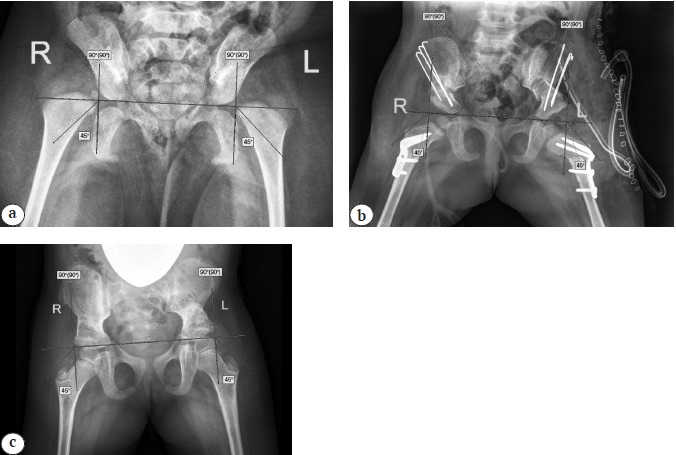

У пациентов первой подгруппы после ОВБ, КОБ, ПОС хорошие результаты лечения были получены в 4 (50%) случаях, а также по 2 (по 25%) случая удовлетворительных и неудовлетворительных результатов. После операции ОВБ у больных первой подгруппы только в 1 (17%) наблюдении отмечен хороший результат, в 3 (50%) случаях — удовлетворительный и в 2 (33%) наблюдениях– неудовлетворительный. Таким образом, у пациентов первых подгрупп операция ОВБ, КОБ, ПОС позволила получить значимо лучшие результаты лечения, чем операция ОВБ, что обусловлено лучшим как функциональным, так и рентгенологическим состоянием ТБС (р = 0,043) (рис. 4).

Рис. 4. Рентгенограммы таза в прямой проекции пациентки 2 лет из первой подгруппы: a — до операции; b — интраоперационная рентгенограмма после ОВБ, КОБ, ПОС; c — через 2 года после операции / Fig. 4. X-ray of the hip joints in the A–P view in a 2-year-old patient from subgroup 1: a — before surgery; b — intraoperative X-ray after hip open reduction, femoral osteotomy, and Salter innominate osteotomy; c — 2 years after surgery